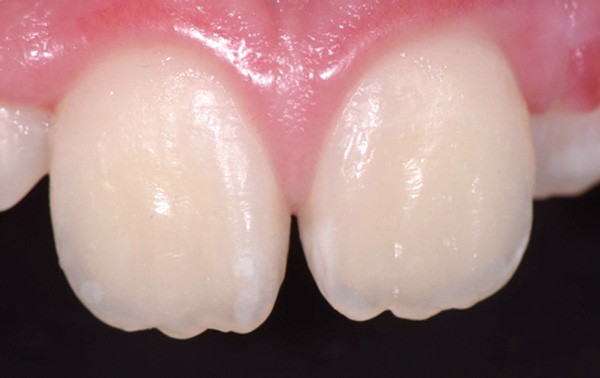

Traitement ultra-conservateur des taches de l’émail : bilan avec 5 ans de recul

Jean-Pierre Attal, Gil Tirlet (Paris)

Les auteurs de cette conférence nous proposent un algorithme pour résoudre le problème des taches blanches de l’émail. Ces techniques sont désormais utilisées avec succès depuis 10 ans. Tout d’abord il convient souvent de réaliser un éclaircissement préalable : celui-ci diminue le contraste entre la tache et le reste de la dent. Ensuite, avant de poser le champ opératoire, il faut choisir la teinte du composite qui sera nécessaire à la fin du traitement. Un sablage/fraisage des taches les plus profondes est alors réalisé, en fonction de la profondeur de la tache. Vient alors l’infiltration ou masquage optique, qui fonctionne sur les taches blanches : on passe une solution d’acide chlorhydrique, puis une solution d’hypochlorite de sodium, et si la tache est devenue blanche alors il est possible de passer à l’infiltration par la résine. Enfin, s’il subsiste une concavité visible, un composite viendra la combler. Le polissage clôt alors le protocole(fig. 11 et 12).